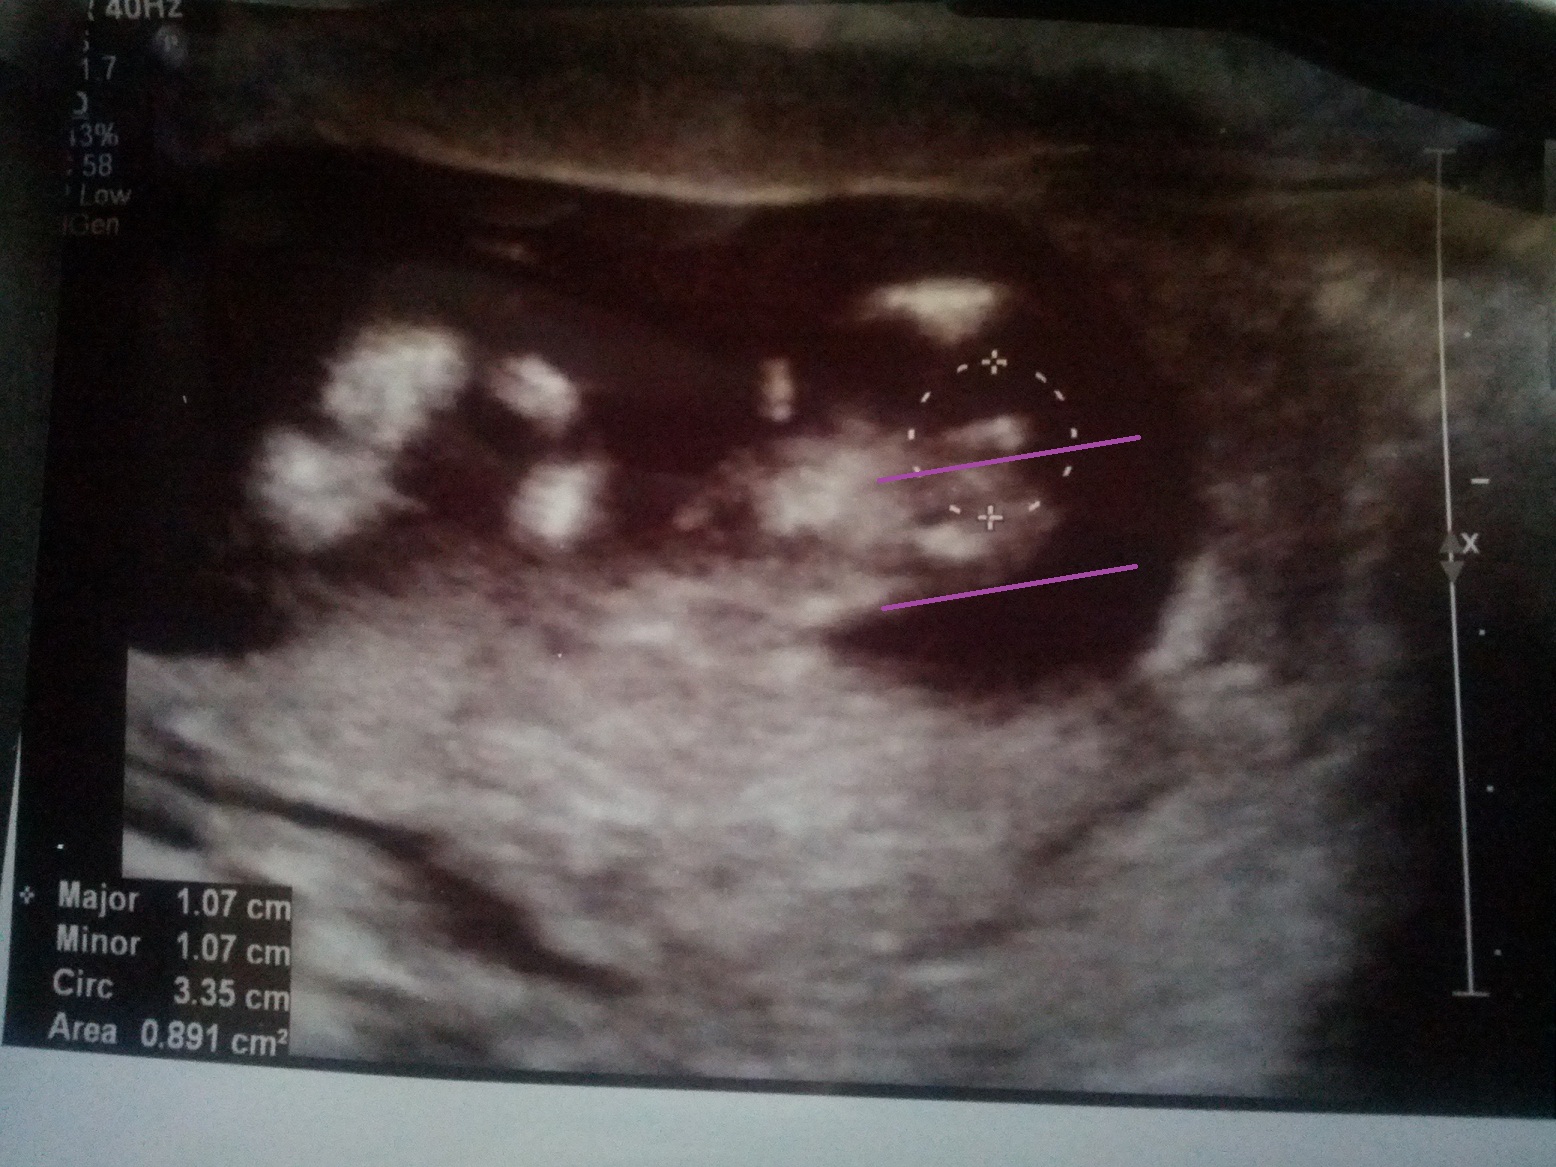

I can't remember if I have responded or not. The nub looks flat to me but it's big so I wouldn't guess girl with much confidence. Did you see a potty shot? This image is not clear either. I cannot really see the other parts clearly to see how baby was positioned for this shot.